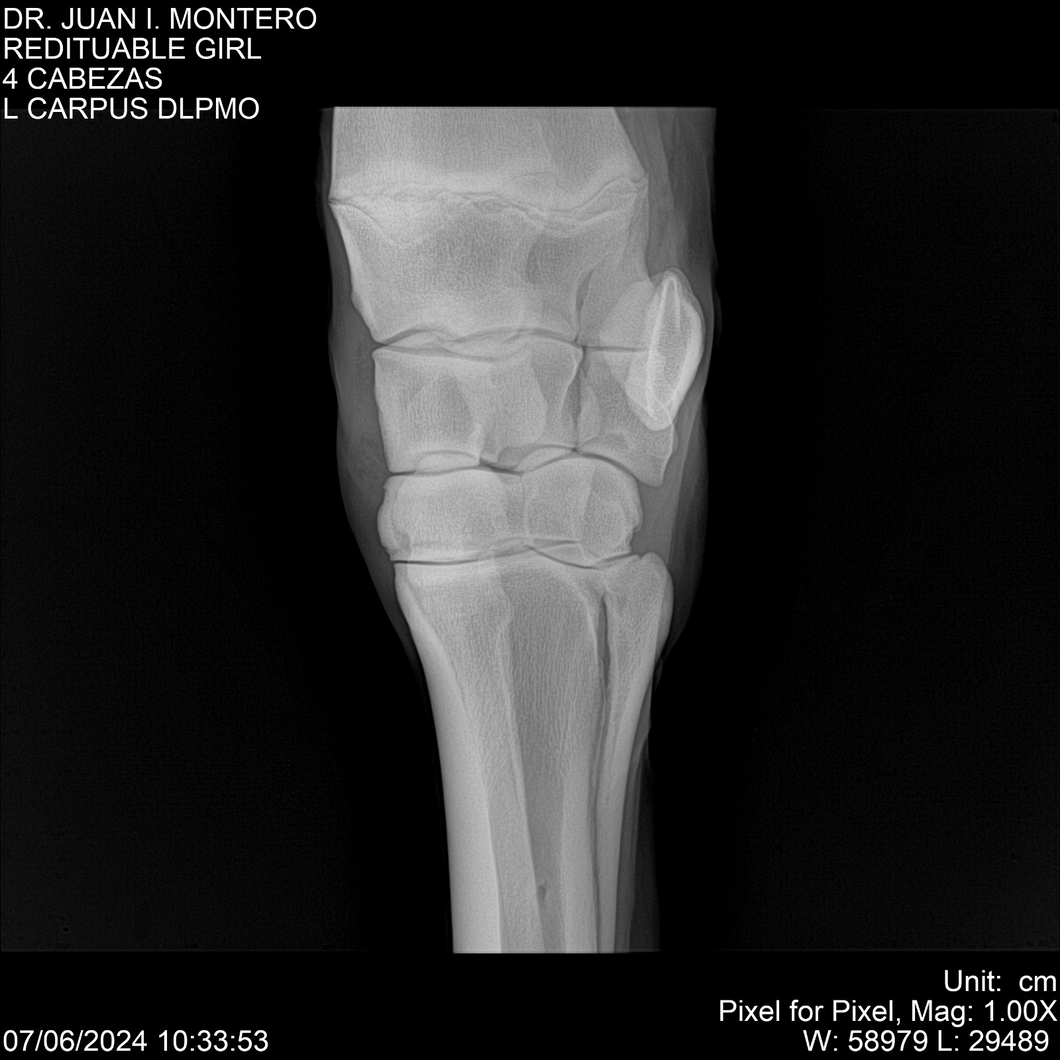

LOTE 19, REDITUABLE GIRL Lote Anterior Volver al remate Lote Siguiente Ficha Contacto Montevideo - Ficha del Lote Identificador: #281096 Categoría: Yeguarizos Montevideo - 79 Visualizaciones ClicData Contacto Empresa: Abelenda N. R., Walter Hugo Nombre*: Teléfono* : E-mail* : Mensaje Enviar Registrese gratis Este contenido Exclusivo está disponible sólo para usuarios registrados Ingresar